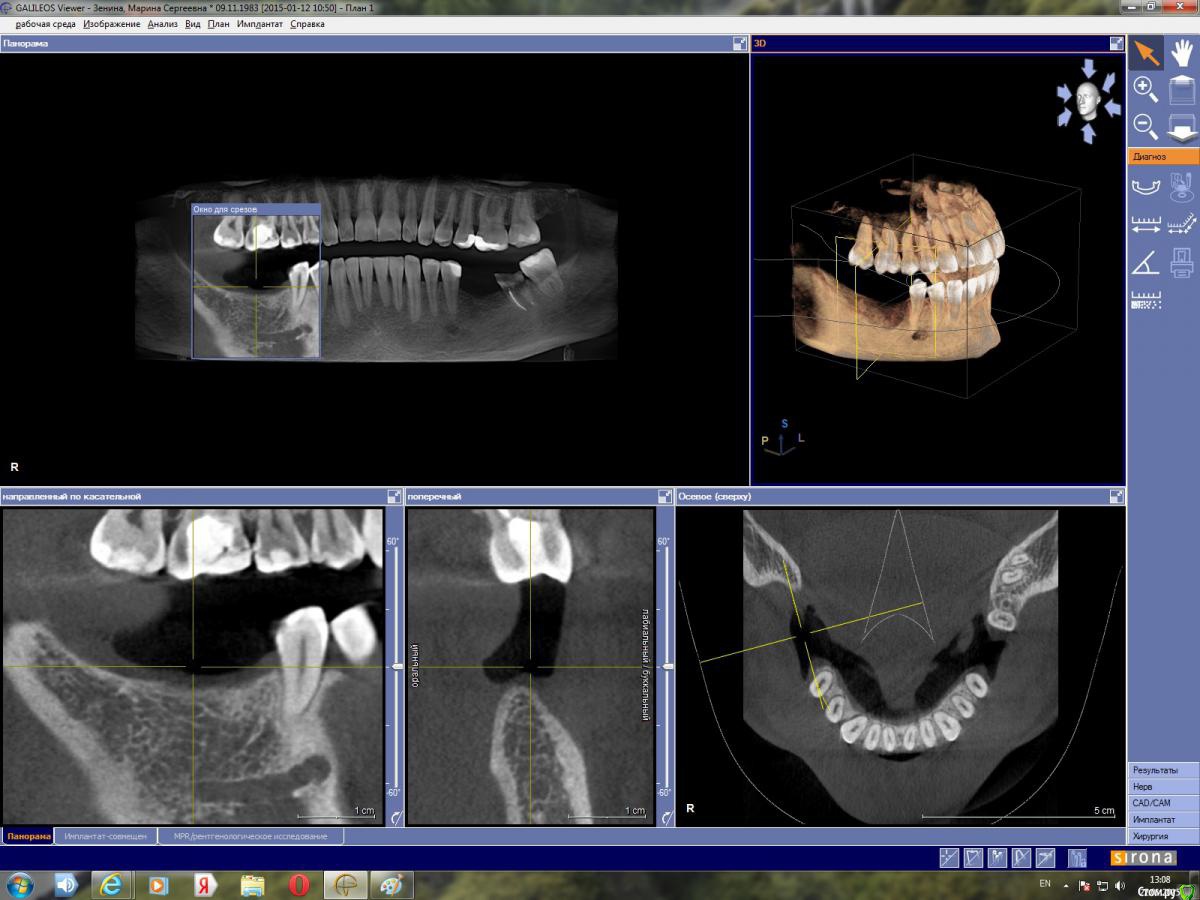

red_butler Опубликовано 22 января, 2015 Поделиться Опубликовано 22 января, 2015 поставьте перекрестие такhttp://i052.radikal.ru/1501/27/c9ad0f50b717.jpg Ссылка на комментарий

марин зенина Опубликовано 22 января, 2015 Автор Поделиться Опубликовано 22 января, 2015 так? Ссылка на комментарий